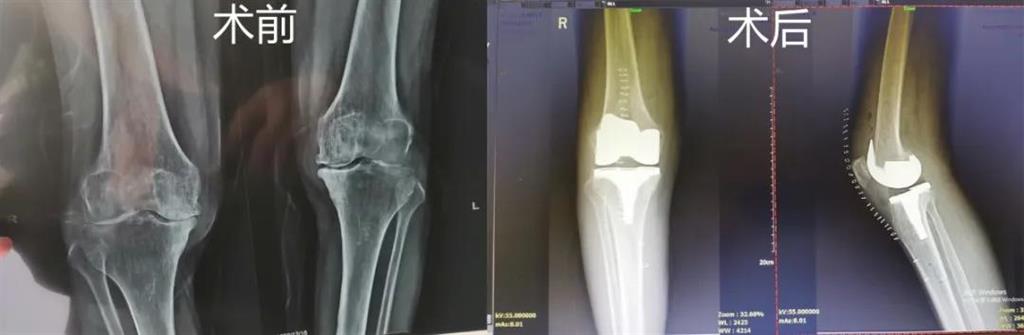

突破!和平國(guó)際醫(yī)院成功完成一例計(jì)算機(jī)導(dǎo)航膝關(guān)節(jié)置換術(shù)

最近,和平國(guó)際醫(yī)院骨科中心開(kāi)展了一項(xiàng)新業(yè)務(wù)——計(jì)算機(jī)導(dǎo)航膝關(guān)節(jié)置換術(shù),而年邁78歲的李奶奶則幸運(yùn)地成為該手術(shù)的首個(gè)受益者。這也是溫州地區(qū)率先將骨科傳統(tǒng)手術(shù)與計(jì)算機(jī)導(dǎo)航系統(tǒng)相結(jié)合應(yīng)用的成功案例,也是和平國(guó)際醫(yī)院骨科中心在膝關(guān)節(jié)置換術(shù)方面所取得的一次重大突破!

李奶奶已經(jīng)被兩側(cè)膝關(guān)節(jié)疼痛困擾了5年左右時(shí)間,尤其是右側(cè)膝關(guān)節(jié),近一年來(lái)癥狀明顯加重,無(wú)法正常生活。經(jīng)過(guò)多方打聽(tīng),一家人來(lái)到和平國(guó)際醫(yī)院。

和平國(guó)際醫(yī)院副院長(zhǎng)、骨科中心主任劉丹在診斷后發(fā)現(xiàn),老人雙側(cè)膝關(guān)節(jié)患有骨性關(guān)節(jié)炎,右側(cè)膝關(guān)節(jié)較為嚴(yán)重,而且關(guān)節(jié)磨損嚴(yán)重,關(guān)節(jié)間隙基本消失。

經(jīng)過(guò)進(jìn)一步檢查后,劉丹帶領(lǐng)團(tuán)隊(duì)在計(jì)算機(jī)導(dǎo)航系統(tǒng)的輔助下,為老人實(shí)施了右側(cè)全膝關(guān)節(jié)置換手術(shù)。術(shù)中出血明顯減少,術(shù)后疼痛腫脹等反應(yīng)輕微,畸形矯正力線恢復(fù)理想,而且功能恢復(fù)快速,術(shù)后四天就可以下地行走。

據(jù)劉丹主任介紹,計(jì)算機(jī)導(dǎo)航膝關(guān)節(jié)置換術(shù)可以避免打開(kāi)股骨髓腔,從而明顯減小手術(shù)創(chuàng)傷減少術(shù)中出血,能夠更精準(zhǔn)地從三維角度調(diào)整手術(shù)截骨方向,恢復(fù)肢體對(duì)線,并能進(jìn)行精確的軟組織平衡,從而使患者獲得良好的術(shù)后功能恢復(fù)。